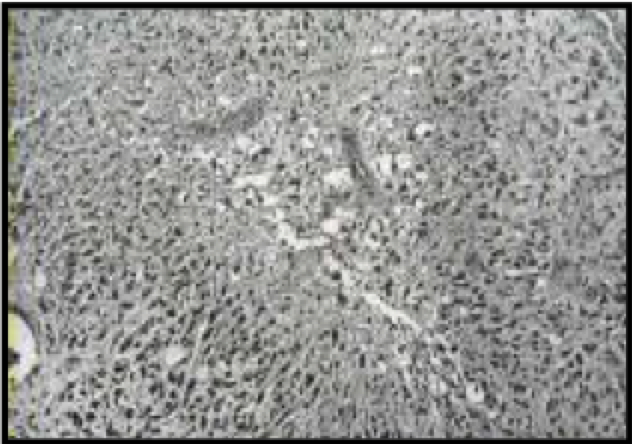

Neoplasma manakah yang dijelaskan pada fotomikrograf di bawah ini (Potongan H & E):

A. Limfoma

B. Medulloblastoma

C. Astrositoma Fibriler

D. Glioblastoma

E. Meningioma

D